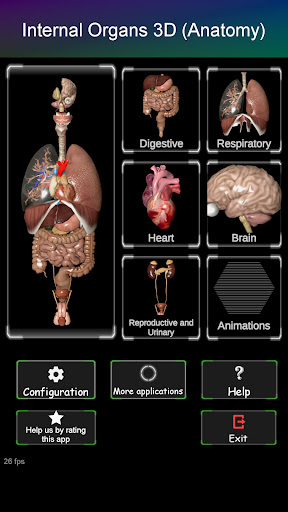

Toont een 3D-anatomisch model van de belangrijkste organen van het menselijk lichaam en een beschrijving van elk orgaan.

Wat zit er in de app?

* Spijsverteringsstelsel, inclusief de maag, dunne darm, dikke darm, en een animatie van dit systeem.

* Ademhalingssysteem, inclusief de luchtpijp, bronchiën, longen en een animatie van dit systeem.

* Voortplantingssysteem, dat de mannelijke en vrouwelijke voortplantingsorganen omvat.

* Hersenen, waaronder de hersenen, het cerebellum en de hersenstam vallen.

* Hart, dat de atria, ventrikels, aorta en een animatie van dit orgel omvat.

Kenmerken:

* Ondersteunde talen: Engels, Frans, Portugees, Spaans, Chinees, Hindi, Russisch, Duits, Japans, Italiaans.

* Gemakkelijk te openen en te navigeren (zoom, 3D-rotatie).

* Verberg of toon informatie.

* Vergelijk mannelijke en vrouwelijke organen.

* Beschrijvingen van elk orgel.

Deze app is ontworpen als aanvulling op de studie van anatomie in verschillende onderwijs-, gezondheidszorg- en culturele omgevingen.

Praktische, nuttige en waardevolle anatomische informatie binnen handbereik.

Download de app vandaag nog en leer anatomie interactief!